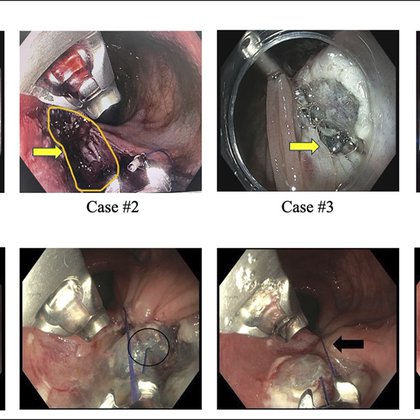

💡 Complete colorectal anastomosis occlusion with no visible lumen? When guidewire passage is impossible, cautery-enhanced LAMS can recreate the tract and avoid repeat surgery. See how the authors managed this month’s #ACGCRJ Editor’s Pick 👇🟦📄 🔗 https://t.co/WotEYUnDEk